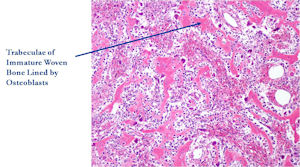

- Interlacing network of bone trabeculae in a loose fibrovascular stroma

- Prominent vessels

- Osteoblasts are plump, active, scattered mitotic figures

- Osteoblasts line up around periphery of trabeculae (Osteoblastic Rimming)

- Soft tissue component usually surrounded by shell of reactive bone or periosteum (Egg Shell Rim of Calcification)